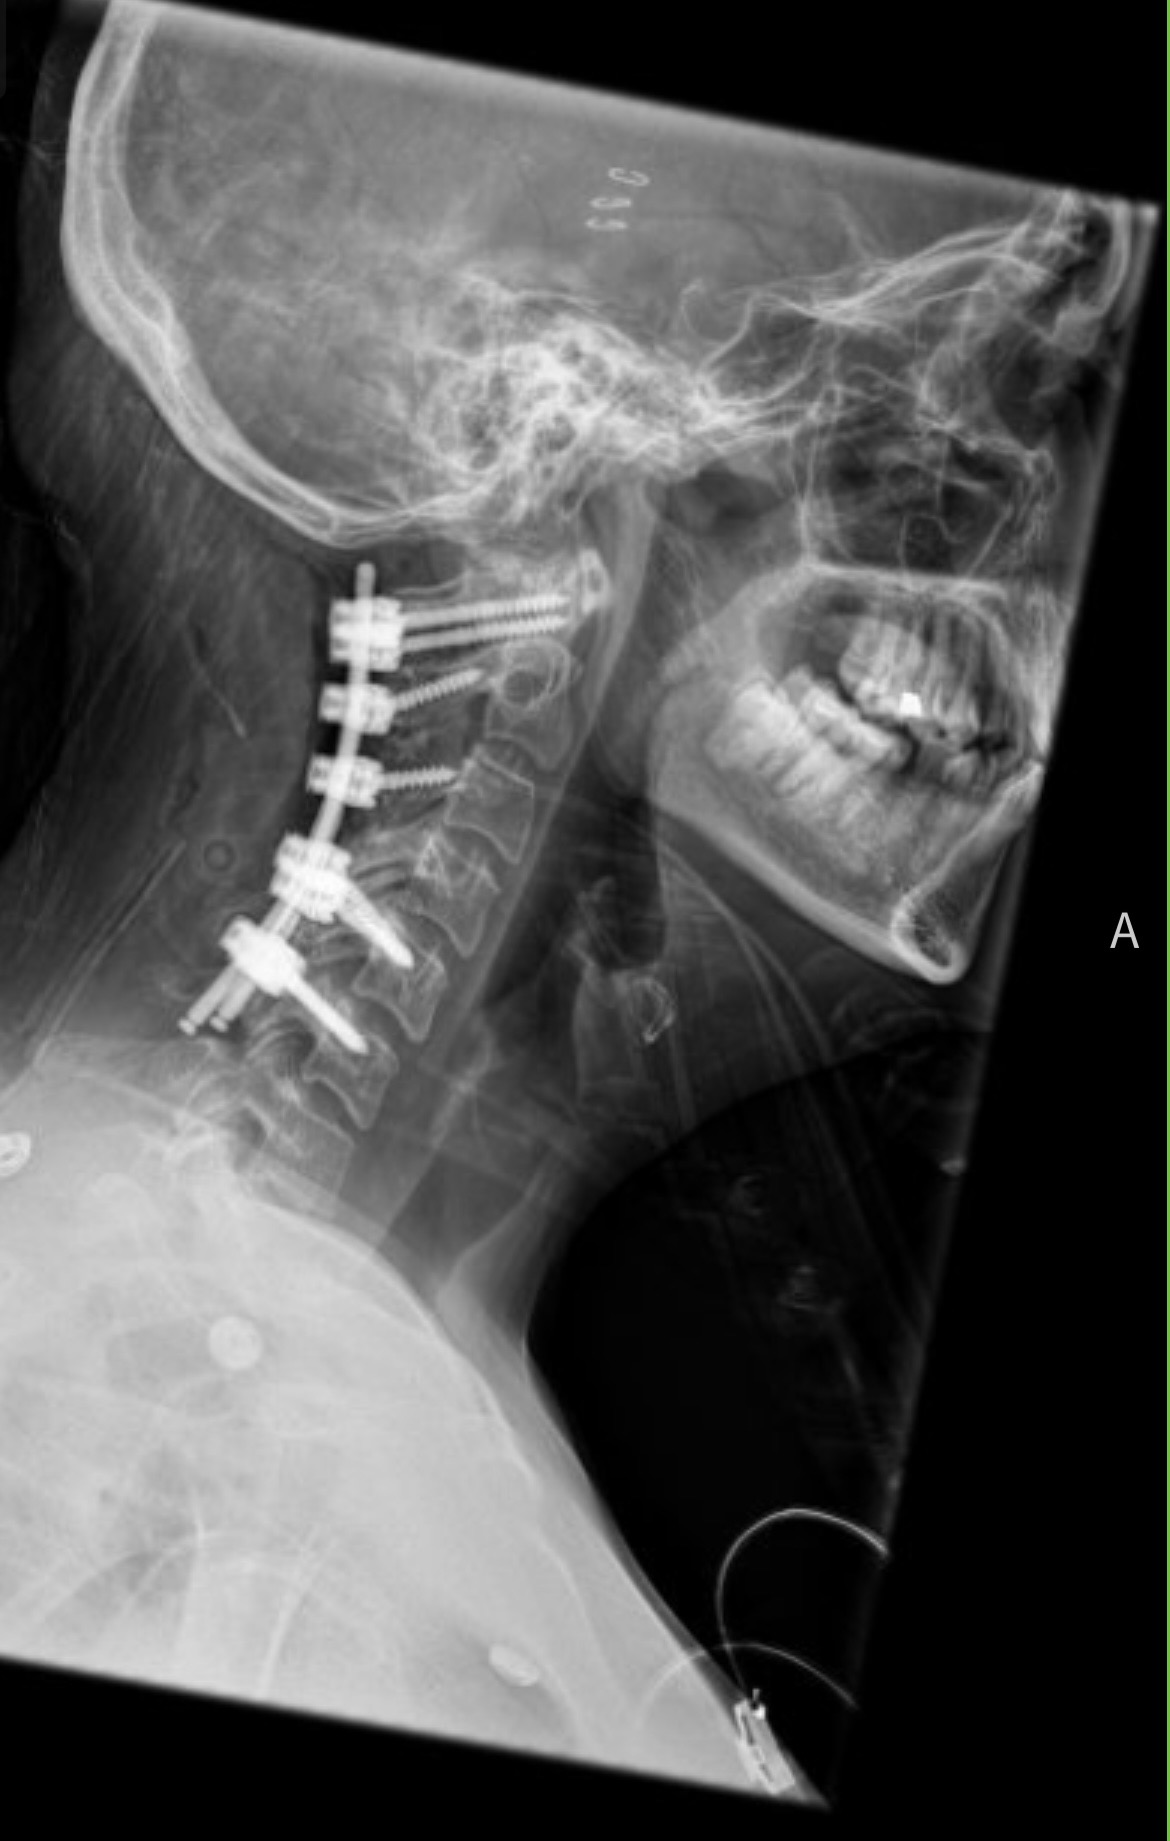

In the fall of 2025 I had surgery to remove two tumors on my thoracic spine, fusing 6 of my vertebrae and significantly limiting my mobility. Just one month later, I had an additional surgery to have a tumor (fibroma) removed from my left leg. This being just a few inches higher and located on the same nerve as a previous sarcoma, post-op and continued recovery has been especially difficult both physically and mentally as I battle to recover from past and present trauma.

The reason for me needing all of these surgeries is because I was born with a silly little thing called Neurofibromatosis Type 1 (NF1), a genetic condition that causes tumors to grow on the nerves throughout my body. They are generally benign, and fortunately this was the case with my recent surgeries.